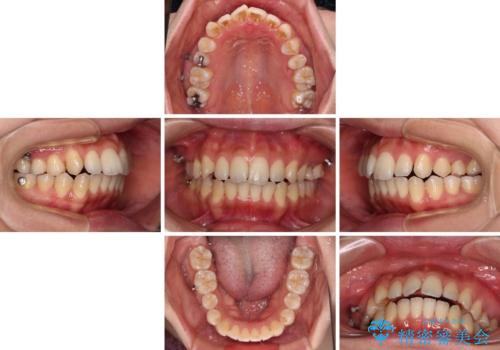

乳歯を抜歯し、舌側の永久歯を引っ張り出すこととしましたが、希望のインビザラインでは移動量が大きすぎて対応できない可能性があったため、ワイヤー装置にて改善することとしました。

ワイヤー装置にてある程度歯列が改善されたところで、上下をインビザラインにて矯正治療を行うこととしました。